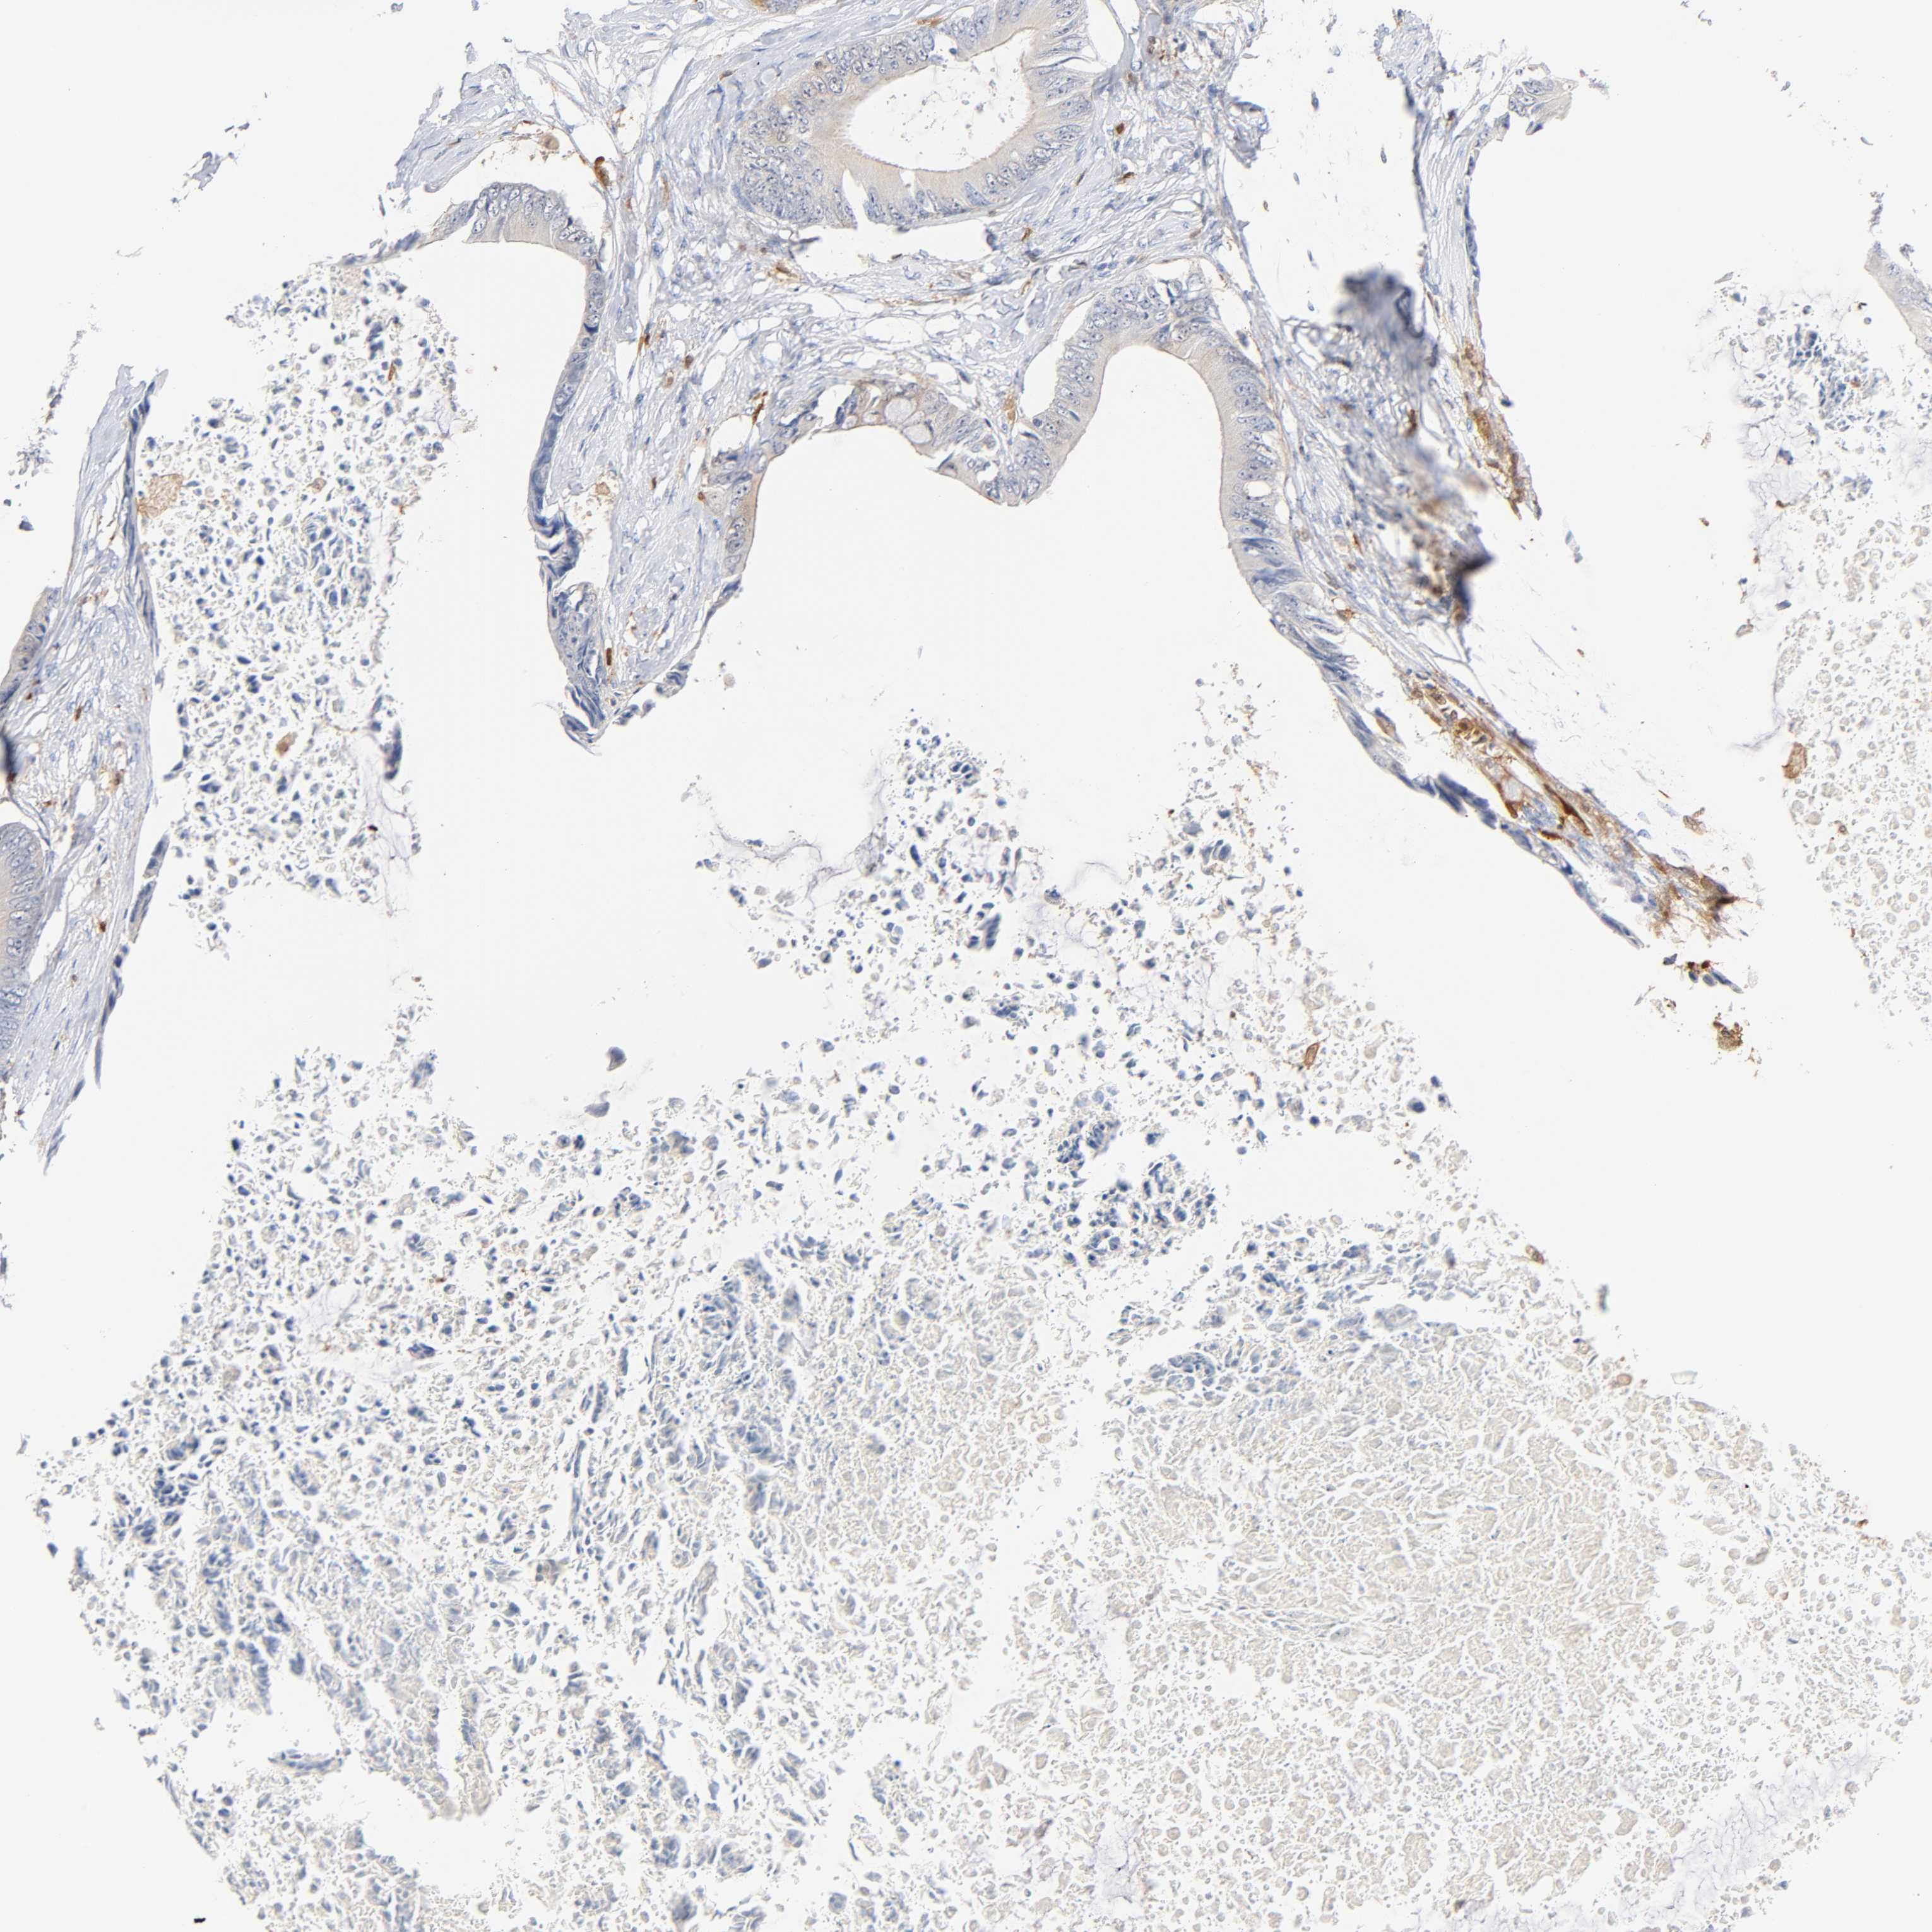

CANCER COLORECTAL CANCER Show tissue menu

Colorectal cancer

Human cancer